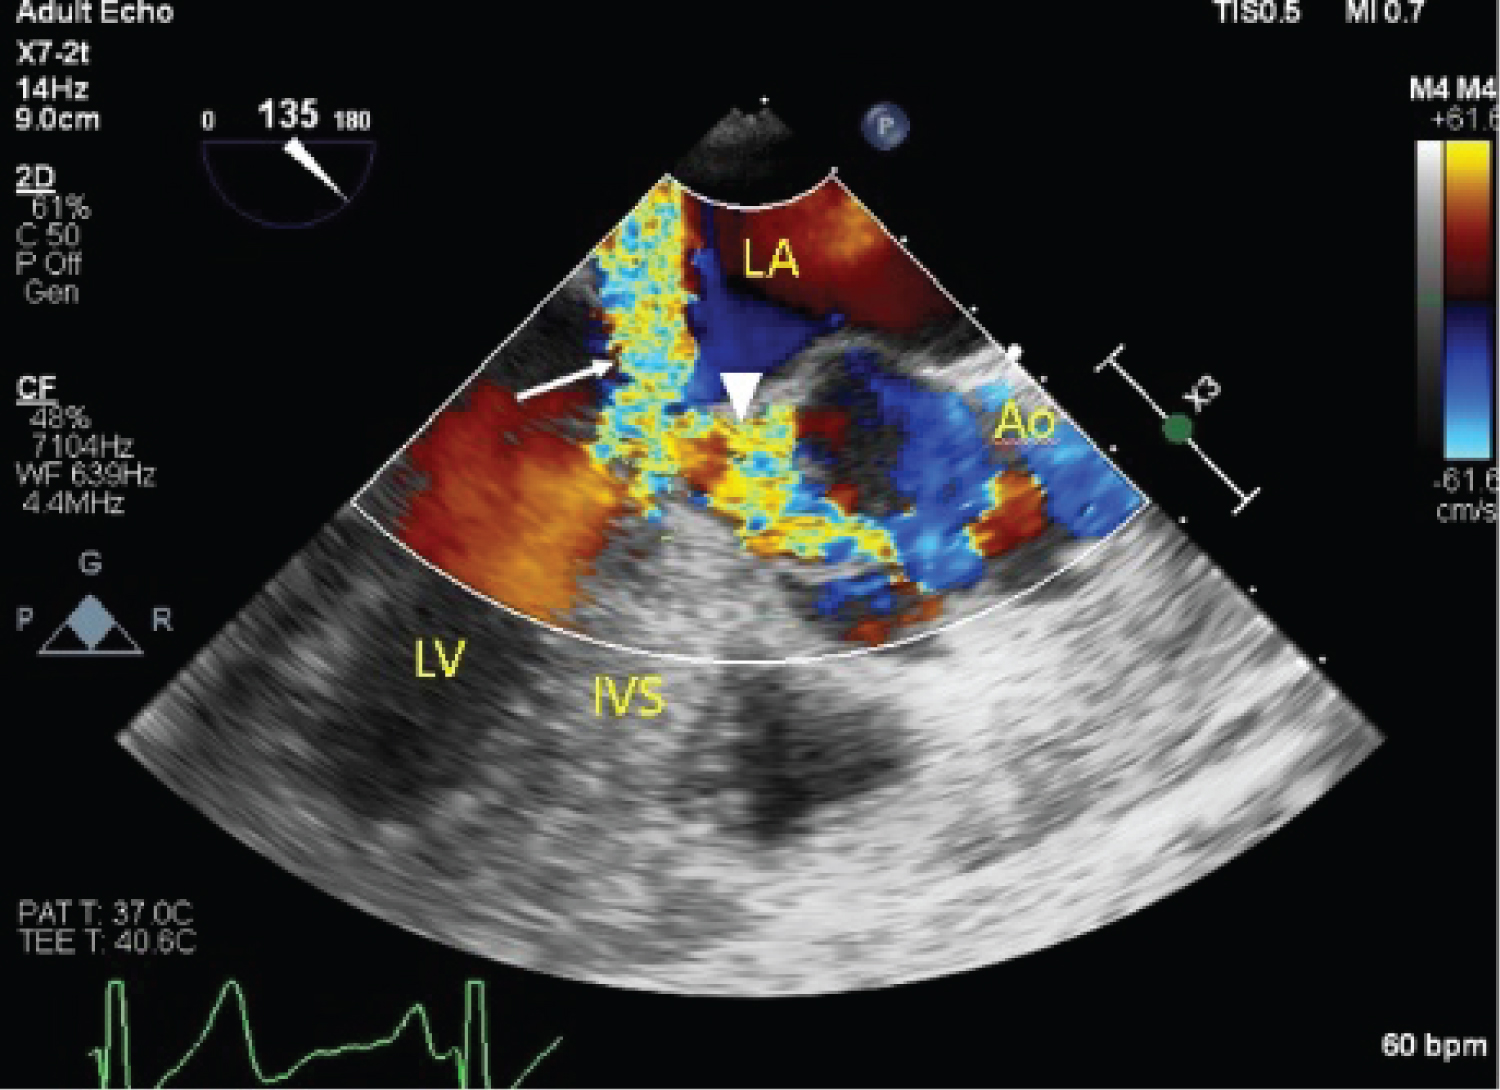

Her case was discussed with the cardiothoracic surgical team, and the decision was for single-vessel coronary artery bypass with left atrial mass excision and mitral valve repair. Intra-operative trans-esophageal echocardiogram showed systolic anterior motion of the mitral valve, with resultant severe mitral regurgitation (Figure 6). The maximum resting intra-left ventricle gradient was measured at 72 mmHg. A well circumscribed mass was attached to the inferior-posterior left atrial wall, in keeping with a known left atrial myxoma. Single vessel coronary artery bypass grafting of the left internal mammary artery (LIMA) to the 2nd diagonal artery with excision of the left atrial myxoma was performed, followed by mitral valve repair with an Alfieri stitch applied from the A2 to P2 mitral leaflets (Figure 7). Immediate post-operative trans-esophageal echocardiogram showed reduction in mitral regurgitation to mild severity with reduction in systolic anterior motion of the mitral valve (Figure 8 and Figure 9). Peak pressure gradient across the left ventricular outflow tract was reduced to 27 mmHg. The patient made an uneventful recovery, and repeat transthoracic echocardiography done on post-operative day 10 showed satisfactory trans-mitral gradient of 3 mmHg with resolution of the prior systolic anterior motion of the mitral valve. There was non-significant left ventricular outflow tract gradient of 28 mmHg at rest. She was discharged the following day.

Figure 6: Intra-operative TEE showing LVOT obstruction (arrowhead) and severe mitral regurgitation (arrow). View Figure 6